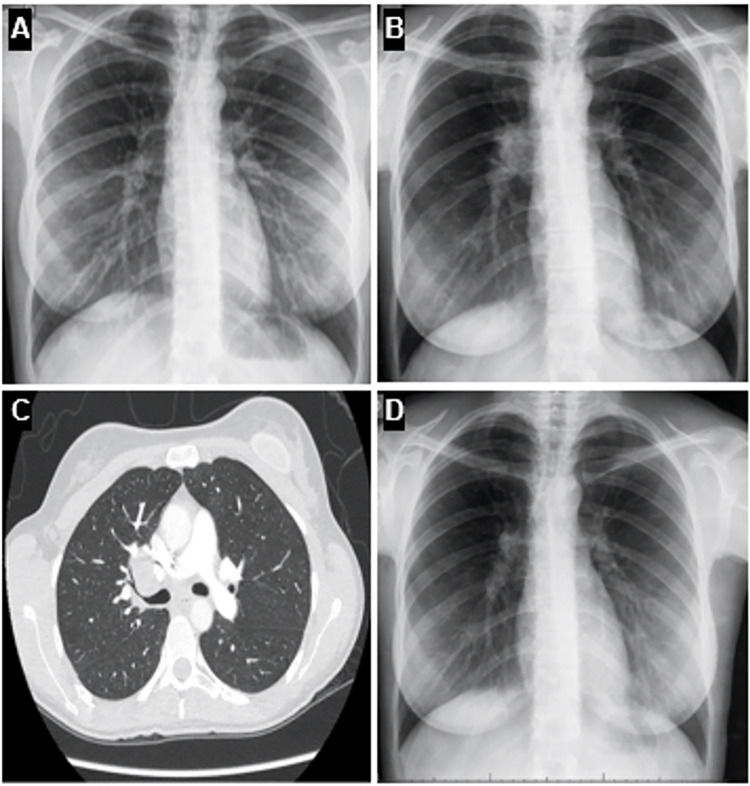

Behçet's disease (BD) is a chronic and multisystem disorder characterized by recurrent oral and genital ulcers, along with ocular, cutaneous, vascular, gastrointestinal, and neurologic manifestations. The etiology is thought to involve an autoimmune response triggered by infectious or environmental factors in genetically predisposed individuals. Mycobacterium tuberculosis has been proposed as a potential trigger for BD, although this association remains rarely reported. We show a compelling case of a patient with BD diagnostic criteria who subsequently developed mediastinal tuberculous lymphadenitis, which was initially suspected as disease activity. This case underscores the importance of considering tuberculosis in BD patients with new or worsening symptoms despite appropriate therapy.